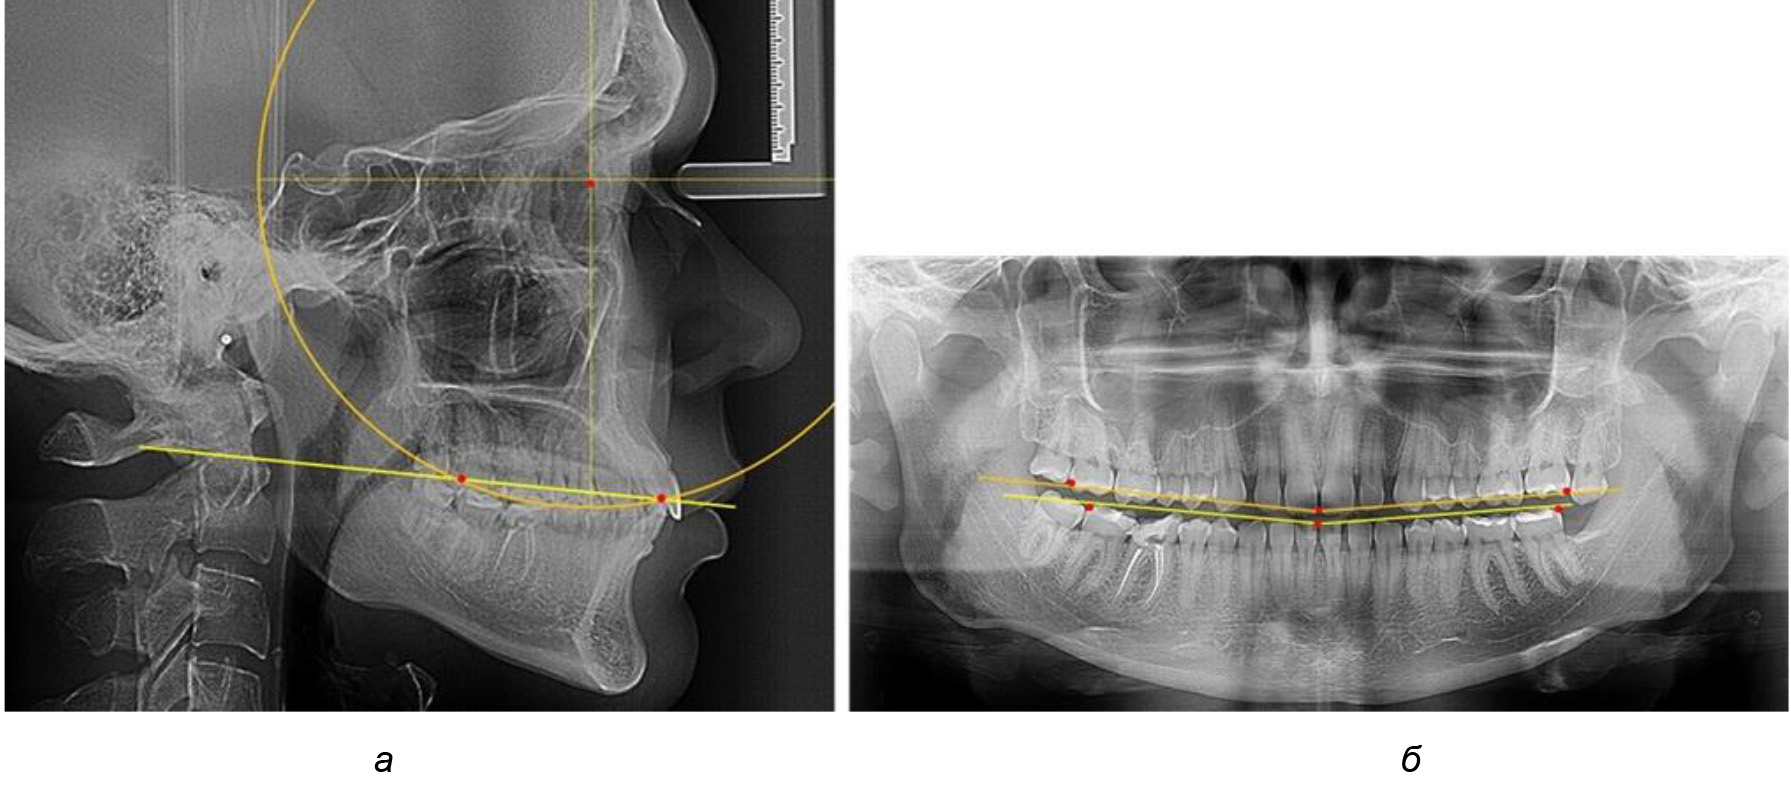

При анализе латеральных ТРГ устанавливали реперный окклюзионные точки в переднем и боковом отделе. Передняя точка устанавливалась на режущем крае нижнего медиального резца, которую в клинике ортодонтии обозначают как vPOcP. Дистальная точка второго нижнего моляра обозначалась как hPOcP. Измеряли расстояние между окклюзионными точками, что определяло сагиттальный размер окклюзионной линии. Использование программ PowerPoint позволило проводить окружность, проходящую по линии смыкания зубов через окклюзионные точки. Измеряли радиус окружности. Учитывая вариабельность размеров окклюзионной линии и радиуса окружности, определяли относительный показатель через отношение радиуса круга к длине сагиттального размера окклюзионной линии. Глубину окклюзионной кривой измеряли от точки наибольшей выпуклости до окклюзионной линии (рис. 1). На ортопантомограмме (ОПТГ) также соединяли окклюзионные точки правой и левой стороны и измеряли глубину окклюзионной кривой от точки наибольшей выпуклости до окклюзионной прямой линии. Результаты глубины кривой Spee сравнивали по данным ТРГ и ОПТГ.

Рис. 1. Метод определения кривой Spee на ТРГ (а) и на ОПТГ (б)

Деление величины радиуса круга к длине окклюзионной линии составило 1,623 ± 0,02. Таким образом, для определения радиуса окружности, соответствующей кривизне окклюзионного контура боковой ТРГ, необходимо измерить расстояние между передней и задней окклюзионными точками и последующим умножением полученной величины на число Фибоначчи (рис. 2).

Рис. 2. Особенности кривой Spee на ТРГ (а) и ОПТГ (б) у людей с признаками вертикального роста